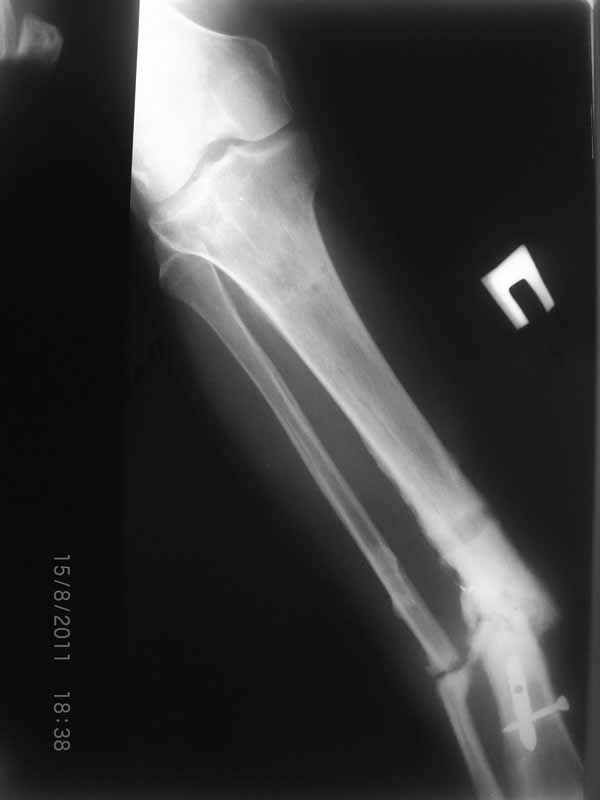

Первично у пациента травма в марте 2009г, когда в результате ДТП получил открытый оскольчатый перелом обеих костей правой голени на границе средней и нижней трети. При поступлении - скелетное вытяжение, затем по заживлению раны произведен остеосинтез пластиной. Со временем (точное время сказать затрудняется) пациенту разрешили полную нагрузку на конечность. Через год после операции пластина сломалась, в связи с чем пластина удалена и установлен интрамедуллярный гвоздь. Через 2 месяца разрешили полную нагрузку и гвоздь сломался. В сентябре 2010 произведено наложение спицевого компрессионно-дистракционного аппарата. В мае 2011 появилось отделяемое в местах проведения спиц, в связи с чем аппарат демонтирован. Правая голень временно иммобилизирована гипсовой повязкой, разрешена нагрузка на правую нижнюю конечность. После снятия повязки - клиника ложного сустава обеих костей правой голени. В настоящее время отмечается угловая деформация правой голени на границе средней и нижней трети с отклонением оси в медиальную сторону. Кожные покровы изменены за счет трофических нарушений(имеют более темную окраску по сравнению со здоровой ногой)На коже рубцы на месте проведения спиц.Движения в коленном и голеностопном суставах в полном объеме безболезненны. Пульсация артерий на стопе отчетливая, выпадение чувствительности от третьего луча в латеральную сторону по тылу стопы. В таком виде пациент оказался у нас. Рады выслушать предложения о тактике лечения.